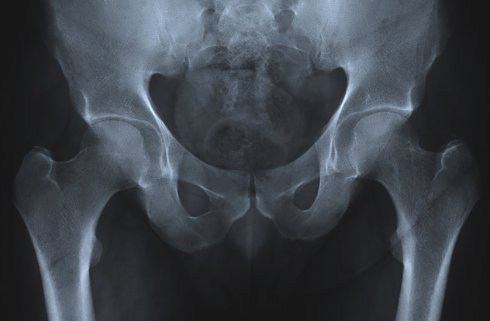

Старение неизбежно сопряжено с появлением массы физических проблем. Общий пример — остеопороз, потеря костной массы и плотности. Он приводит к неизбежным переломам костей, сломанным бедрам и выступающим горбам. Тем не менее группа людей обладает уникальным геном, в котором скрыт секрет лечения остеопороза.

Этот ген был найден у населения африканеров (южноафриканцев с голландским происхождением). Он приводит к тому, что люди наращивают массу костной ткани на протяжении всей жизни, а не теряют ее. Если конкретнее, это мутация в гене SOST, который контролирует белок (склеростин), регулирующий рост костей.

Если африканер наследует две копи мутантного гена, он получает расстройство склеростеоз, который приводит к разрастанию костной ткани, гигантизму, парезу лица, глухоте и ранней смерти. Понятно, что это расстройство хуже остеопороза. Но если африканер наследует только одну копию гена, он просто получает плотные кости на всю жизнь.

Хотя в настоящее время преимуществами этого гена пользуются только гетерозиготные его носители, ученые изучают ДНК африканеров в надежде найти способы обратить остеопороз вспять и другие скелетные расстройства. Основываясь на уже полученных знаниях, ученые начали клинические испытания ингибитора склеростина, который способен стимулировать образование костной ткани.